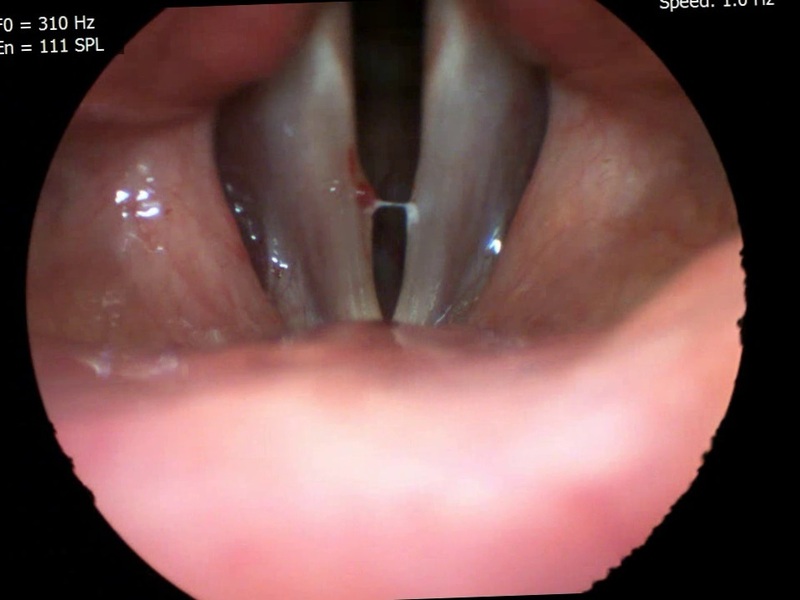

Hyperkinetic Dysphonia

In hyperkinetic dysphonia, the voice is strained [16]; we observe a hard attack, with pneumo-phonetic incoordination associated with the involvement of ancillary muscles (not directly needed for phonation: such as mimics, limb orbicularis, etc.) [8]. In objective examination, though not showing chordal pain, there is protrusion of the false vocal folds, which in adduction tend to cover the true vocal folds until they (false folds) begin to vibrate (hence the phenomenon of bitonality).

In Photo C we can observe the NAT strategy that we suggest for the treatment of hyperkinetic dysphonia, in addition to logopedic therapy.

1 Omega 2 + 2 PMS Sensitive + 3 PMS Motor + 4 Corpus Callosum + 5 Epiphysis. This last point aims to regularise the frequency of vocal fold vibration.

In dysfunctional dysphonia, such as hypokinetic dysphonia and hyperkinetic dysphonia, NAT helps to acquire the right vibrational rhythm of the vocal folds and the right muscle tone and eliminate the anxiety associated with these pathologies.